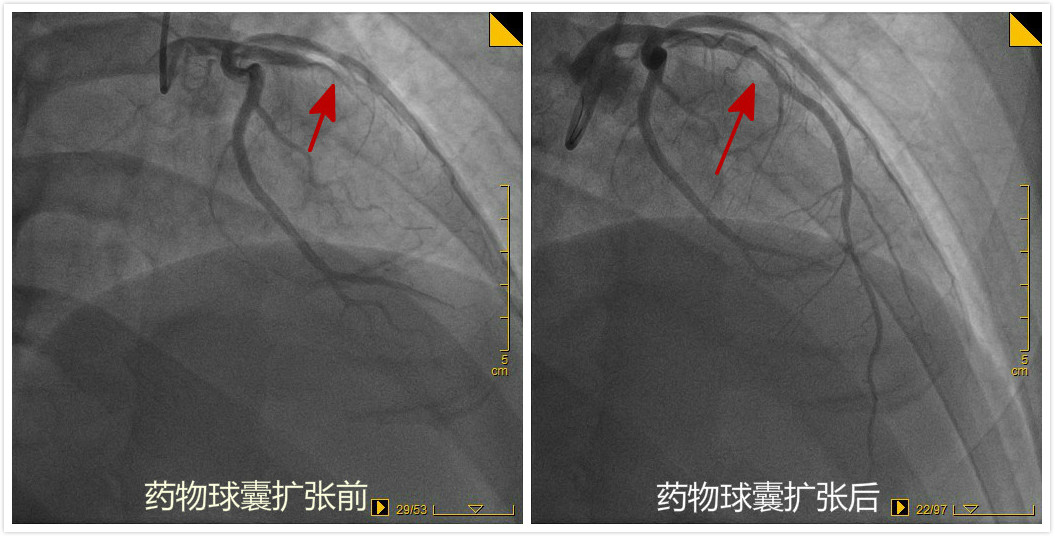

2019年9月17日,桓台县人民医院心内科二病区成功为一例急性心梗患者行急诊药物球囊扩张术。

患者张某,34岁,有高血压,抽烟、喝酒及熬夜的不良生活习惯,工作过程中突发胸痛、大汗,拨打120来到我院。心电图确认为急性前壁心肌梗死,经急诊冠脉造影发现心脏三支血管中最大的前降支完全闭塞,若是采用常规的冠脉内植入支架手术,患者需终生服药。心内科二病区高希春主任综合考虑患者病变特点,决定采用药物球囊扩张术,即把药物贴粘至冠状动脉的病变部位,起到抑制斑块增生的作用,撤出球囊后血管内不留任何异物。手术顺利,目前患者恢复良好。 据高希春主任介绍,随着冠心病发病年轻化,采用单纯药物球囊技术能有效保留血管的舒缩功能,逐渐使血管正常化,同时减少患者术后的出血风险及经济负担。近年来,心内科二病区已成功完成药物球囊术十余例,均取得满意效果。药物球囊成功应用于急性心肌梗死患者,在淄博市尚属首例,桓台县人民医院心内科是目前桓台县唯一能熟练开展此项技术的医院。相信随着该项技术更广泛的应用,必定能造福更多的冠心病患者。